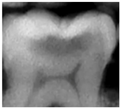

Bitewing radiographs (BW) are usually complementary to the visual-tactile method. These X-rays are, however, not reliable or sensitive enough to detect early non–cavitated occlusal caries due to overlapping topography [13]. When an occlusal carious lesion is detected on a BW, the lesion may have already reached the middle third of dentine, well beyond remineralization interventions [14,15,16].

BW radiographs had been taken by different practitioners with an interval of two years (+/−3 months) (exposure parameters were 70 kV, 7 mA, 0.1620130.20 s). Several digital imaging plates size 2 and CS 7600 scanning system (Carestream Health, Rochester, NY, USA) were used.

In the present clinical study, ICDAS scores of occlusal surfaces based on clinical photographs were compared to scores based on NIRT images and digital intra-oral radiographs. The results show that more early occlusal lesions were detected using NIRT followed by clinical images, while BW scores showed mostly sound surfaces at both examinations (first and second assessments) as shown in Table 3.

The low percentage of carious lesions detected on BWs in our study corroborates the finding of previous studies concerning occlusal carious lesion detection on radiographs. When occlusal lesions are detected on radiographs they usually have reached the middle third of the dentine [41]. Previous studies have shown that BWs have negligible diagnostic value to detect enamel carious lesions and occlusal superficial dentine carious lesions [42,43]. NIRT could therefore be a good adjunct to clinical examination for detecting early occlusal caries. Several studies have suggested that combining the visual examination with another method could improve the accuracy of occlusal carious lesions detection [44,45]. These studies also confirmed the findings of our study.